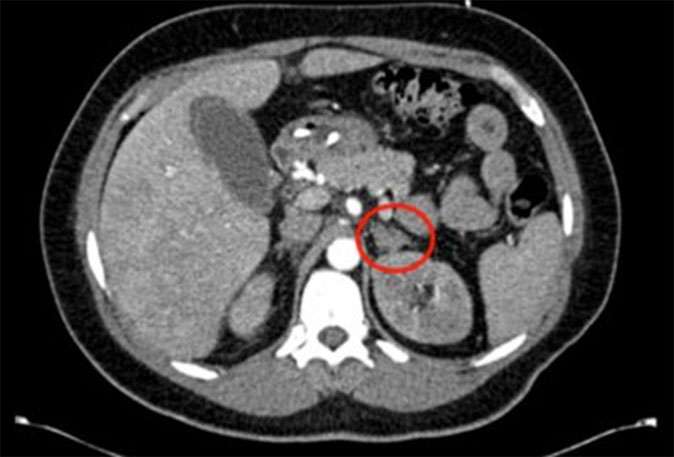

Red circles show small adrenal tumors.